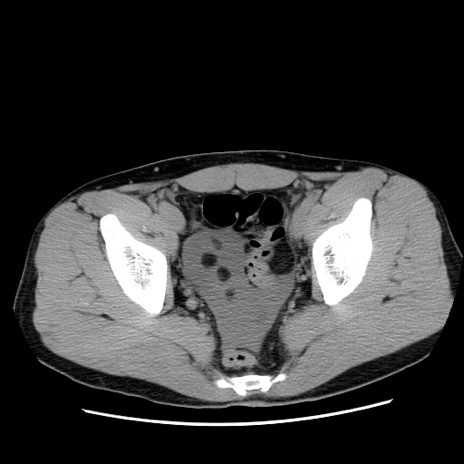

症例36(横断像)

【症例】20歳代 男性

【主訴】心窩部痛

【現病歴】今朝より上腹部痛あり。一旦軽快していたが再度出現したため救急要請。昨日夕に白身の魚を含む刺身を食べた。

【身体所見】BP 136/89mmHg、HR 74/min、BT 37.0℃、腹部:膨満、軟、心窩部に圧痛あり。反跳痛なし、筋性防御なし、腸雑音やや亢進あり。

【データ】WBC 17700、CRP 0.48